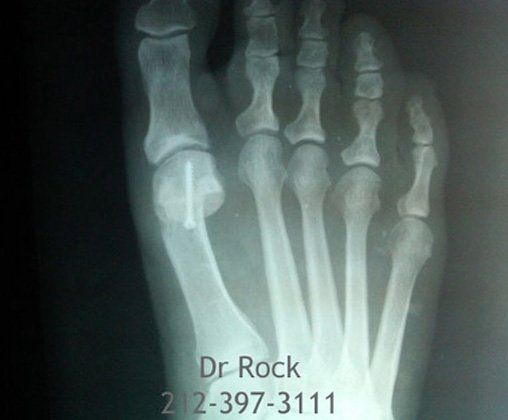

Take a look at our x-ray pictures of our recent footwork and see how your feet can benefit.

for more X-ray photos.